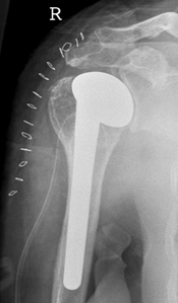

Kop met steel

Hierbij wordt de schouderkop vervangen door een metalen kop met een steel die gedeeltelijk in het bovenarmbot wordt gebracht.

De kom kan vervangen worden door een kunststof kom.

Bij een hemiprothese (halve prothese) wordt alleen de kop vervangen. Bij een totale schouderprothese wordt ook de kom vervangen.

Omdat de kwaliteit van de kom niet altijd van tevoren goed beoordeeld kan worden, wordt vaak tijdens de operatie de beslissing genomen of de kom wel of niet vervangen dient te worden.